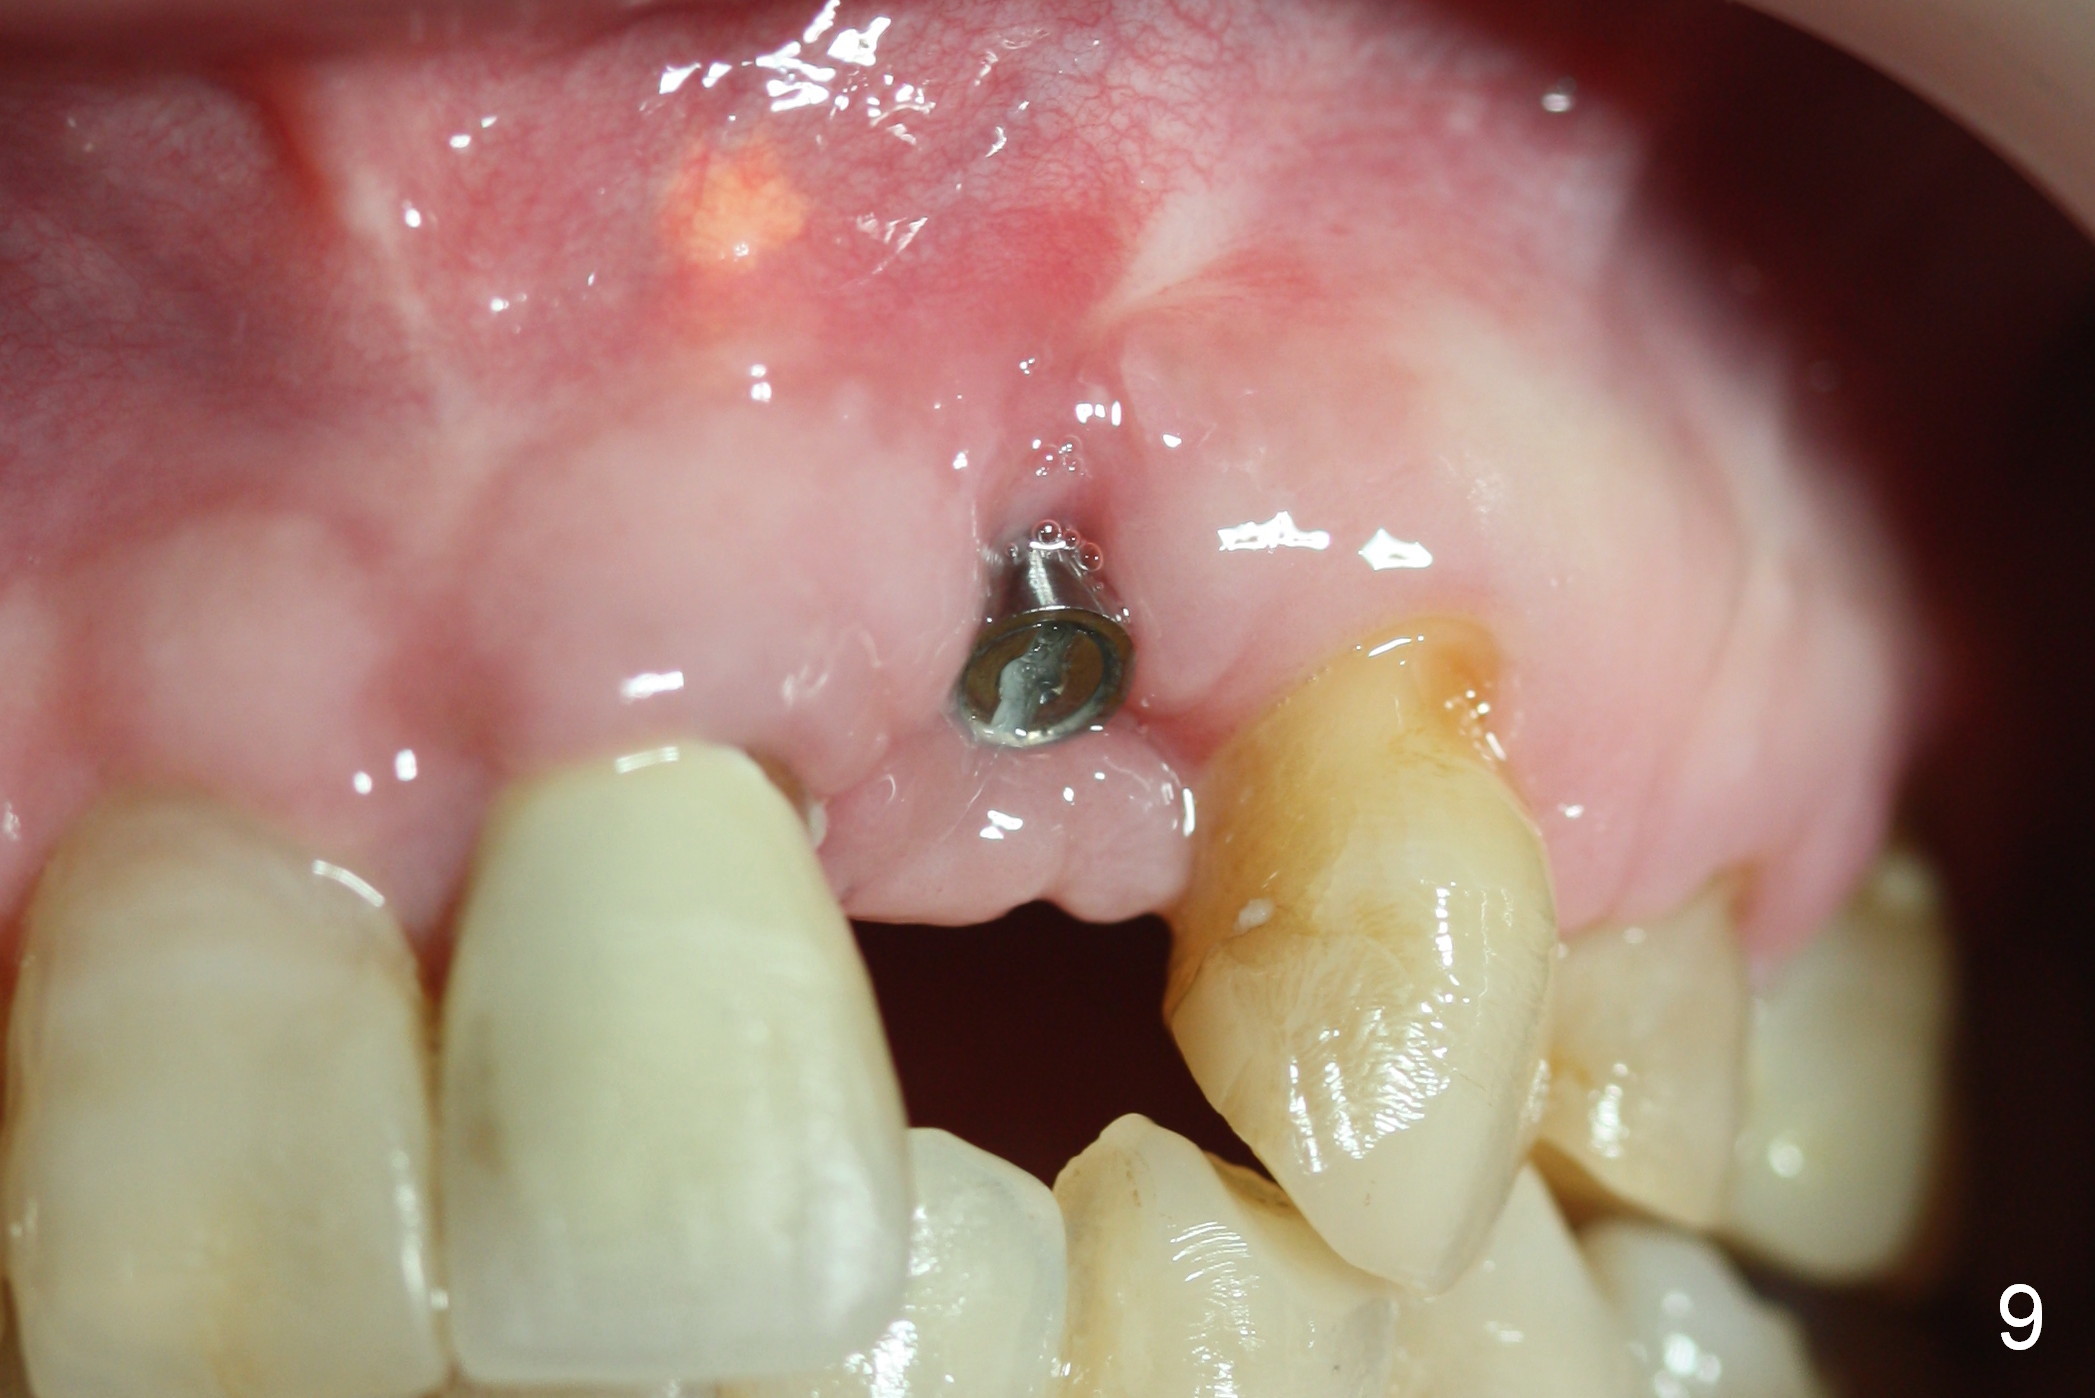

As expected, there is midbuccal tissue deficiency (Fig.9,10: 2 months postop). After discussion, a free gingival graft from the palate is placed (Fig.11,12 *). Two weeks later, the graft sloughs (Fig.13). A pedicled flap is designed (Fig.14) and transferred to repair the defect (Fig.15,16).